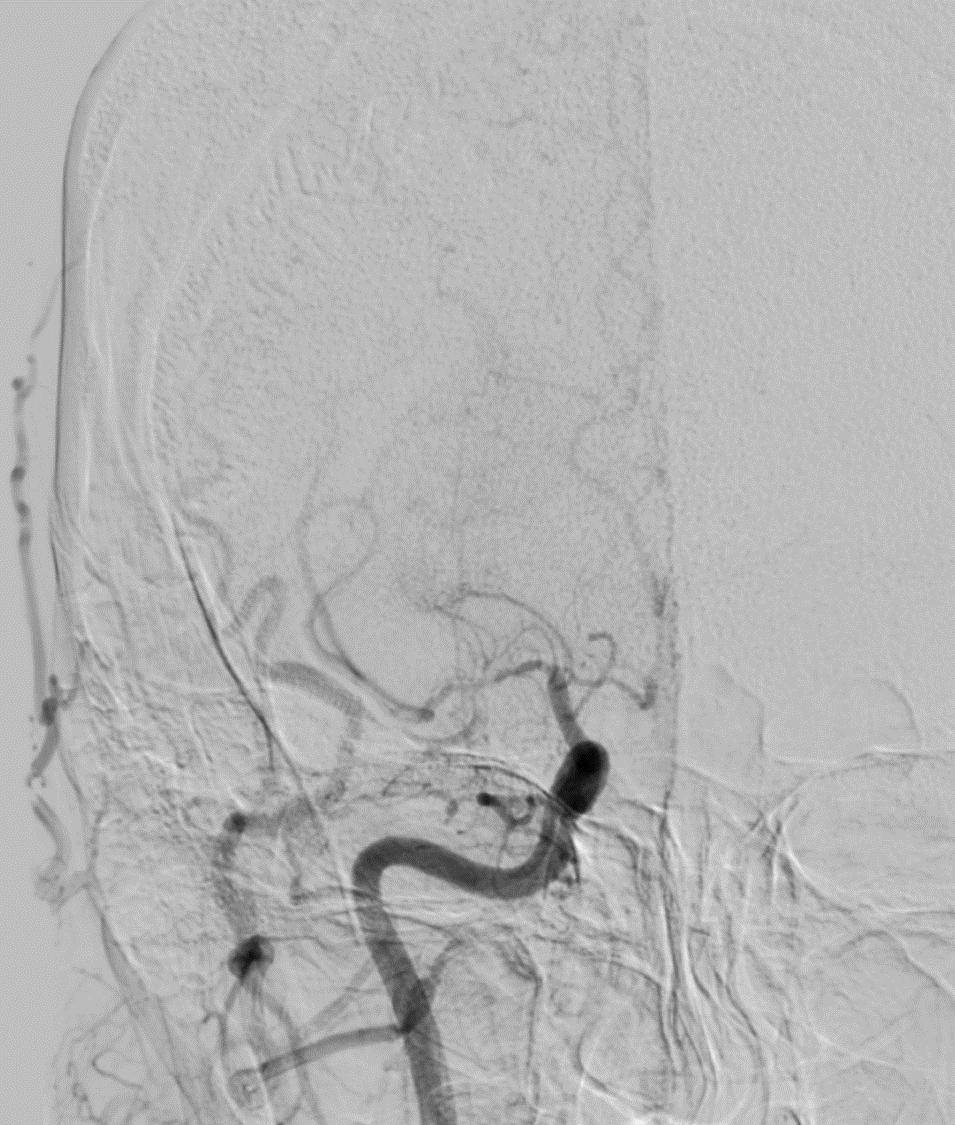

MRV shows left Transverse and sigmoid sinus thrombosis. No improvement after 2 days of IV heparin. Pt requires heavy sedation, ventilation for headache/agitation.

DSA also confirmed the extensive clot. In view of her recent LSCS 20 days ago, we were hesitant about giving IV lytics (urokinase infusion). Hence went in with an ACE 5 Max catheter and sucked out a mountain of clot